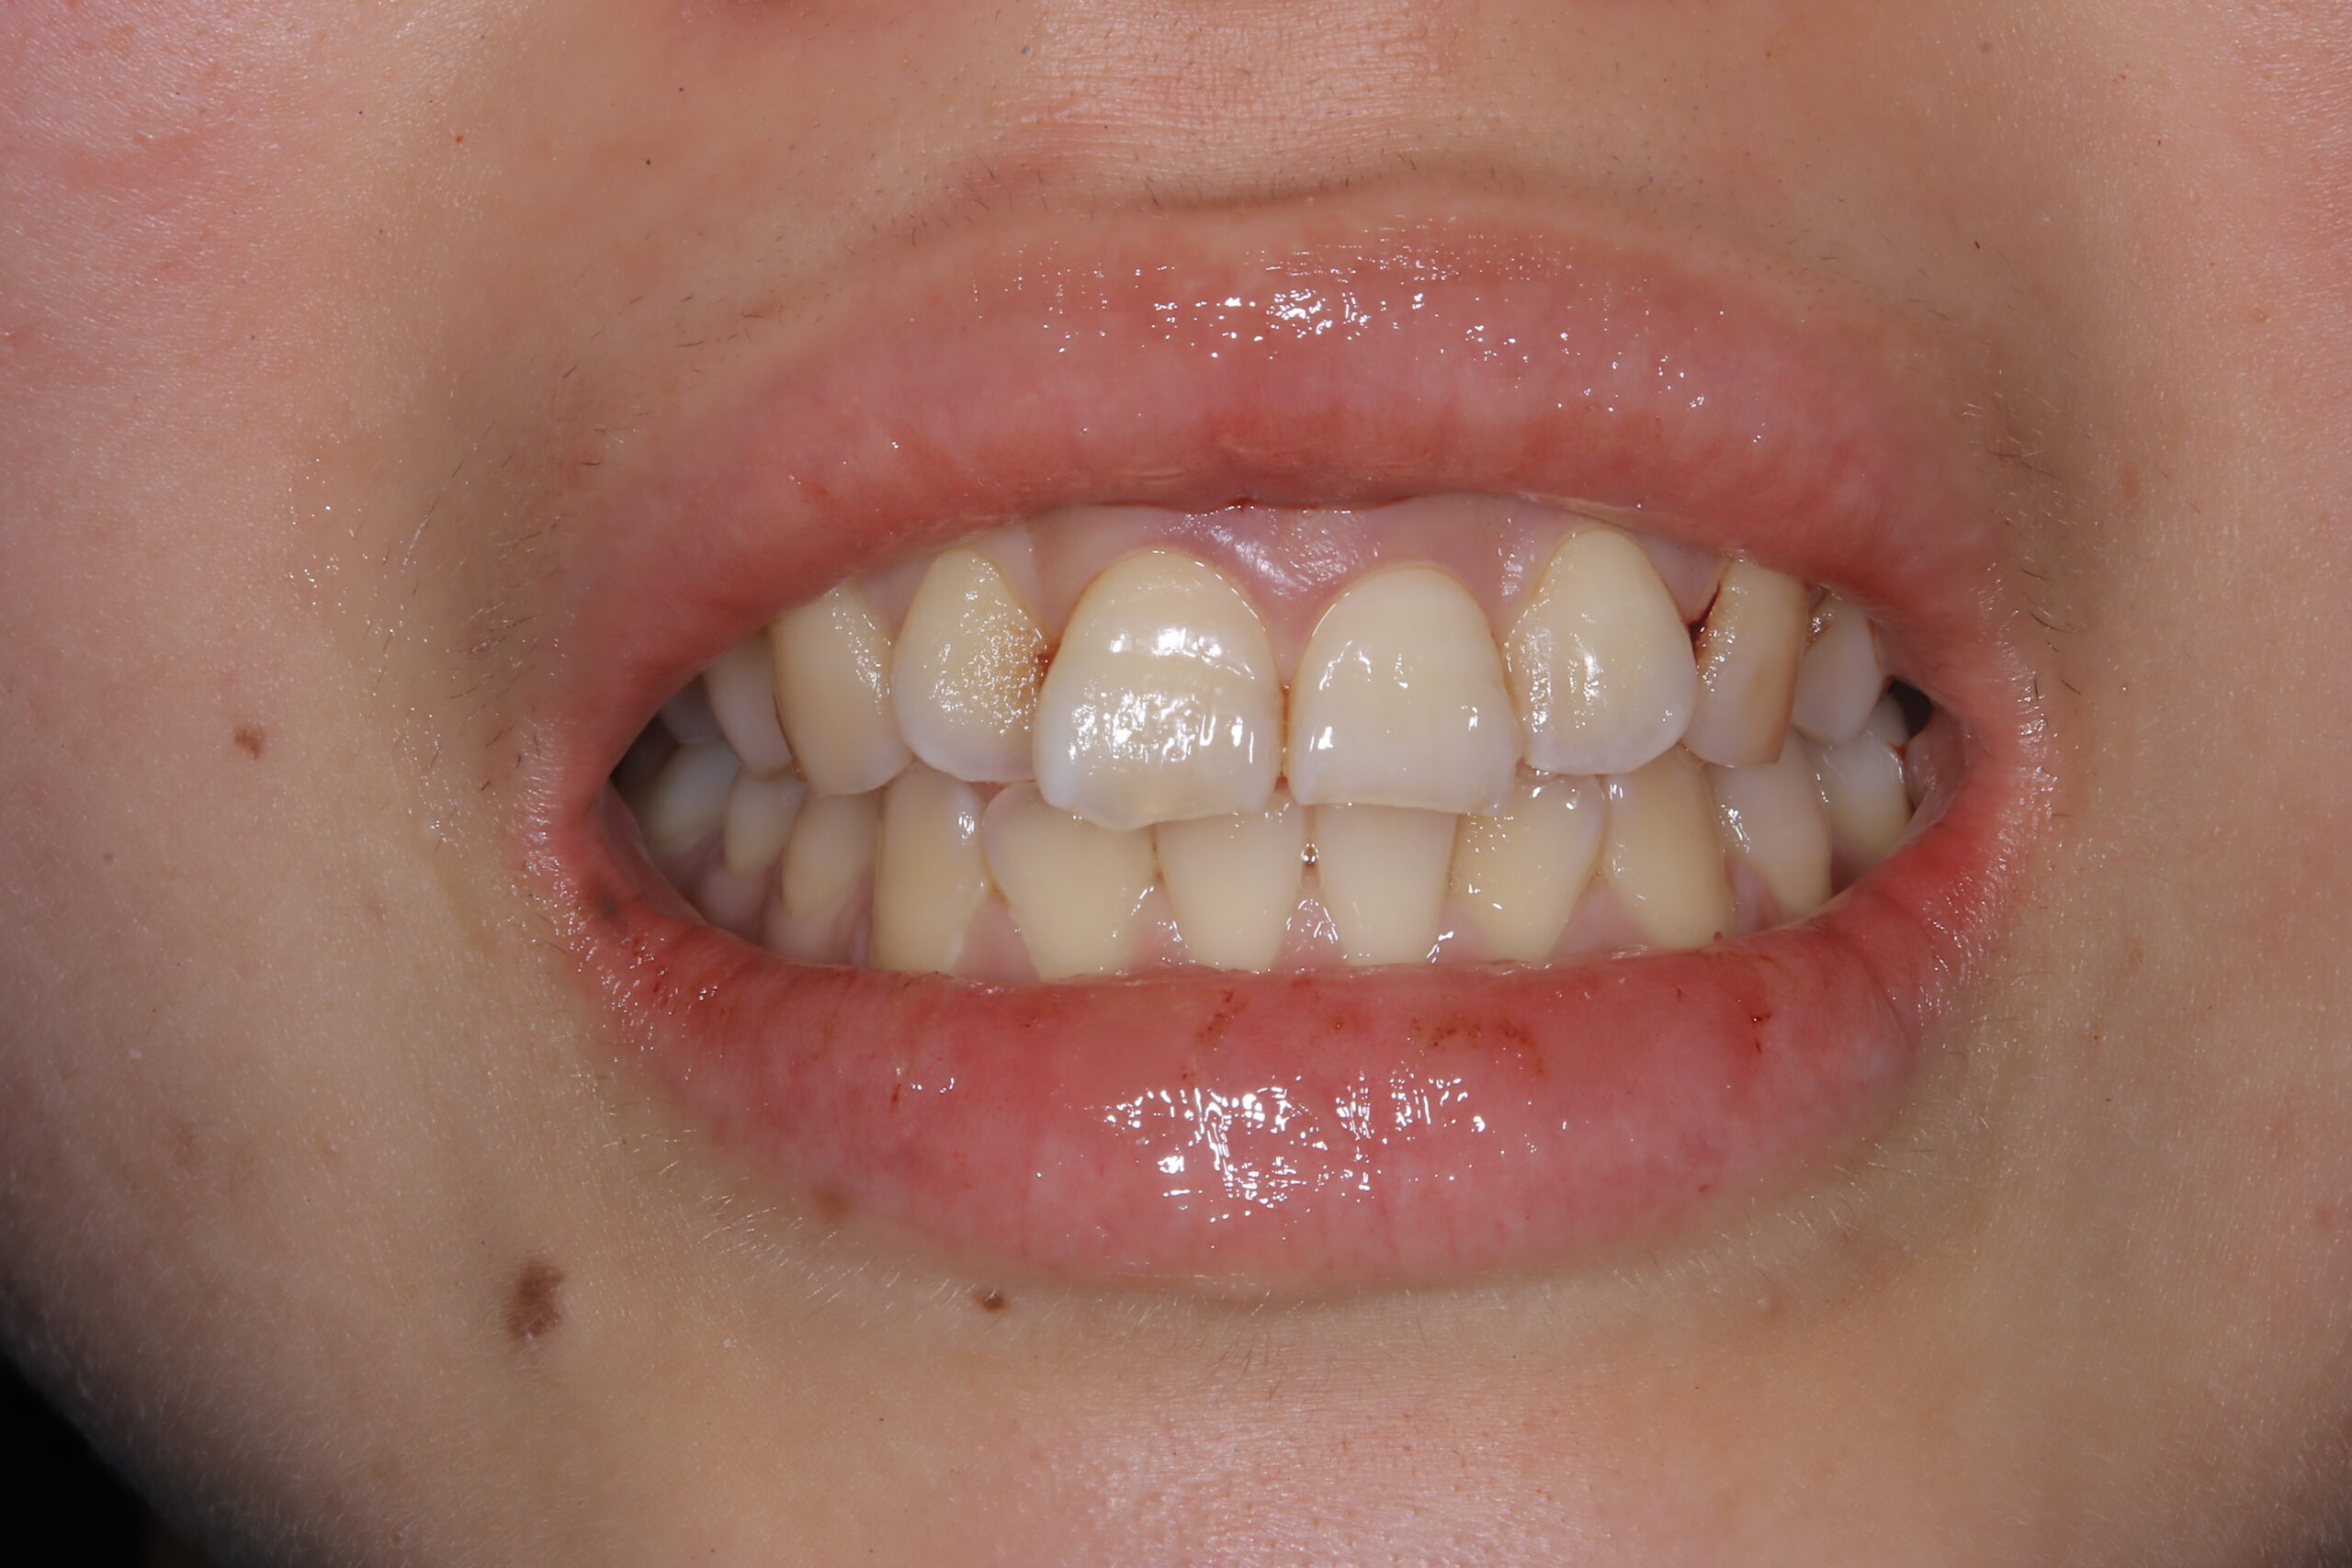

Before

ガミースマイル治療前の状態

患者様は笑うと4.5ミリ歯茎が見える唇が上がりすぎてしまうタイプのガミースマイルでした。